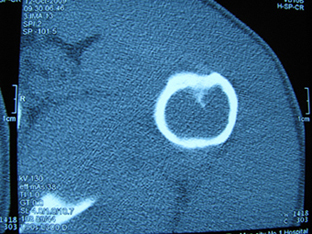

标题: X6404B:肱骨骨质破坏(CT片) [打印本页]

标题: X6404B:肱骨骨质破坏(CT片)

男,50岁,左肩部轻微疼痛,活动不便5个月就诊,近十天加重,无红肿热,间断理疗治疗无好转,既往5个月前左肩轻微拉伤史

骨巨?动脉瘤样骨囊肿?

内生软骨瘤。

内生软骨瘤。

内生软骨瘤?-----------

年纪大了,先要排除转移瘤。

髓腔内软组织肿块并斑片状钙化,考虑高分化软骨肉瘤可能性大。

考虑骨巨或动脉瘤样骨囊肿。

内生软骨瘤可能性大,期待结果。

孤立性骨囊肿。

内生软骨瘤可能性大

其内可见钙化,考虑软骨源性肿瘤,内生软骨瘤可能

但由于年龄较大,恶性软骨肉瘤待排

肱骨头内巨大软组织肿块并斑片状钙化,内生软骨瘤?骨巨细胞瘤?软骨粘液样纤维瘤?期待结果!

髓腔内软组织肿块并斑片状钙化,考虑高分化软骨肉瘤可能性大。

内生软骨瘤可能性大

肱骨头内巨大软组织肿块并斑片状钙化,内生软骨瘤?骨巨细胞瘤?软骨粘液样纤维瘤?期待结果

考虑内生软骨瘤?骨巨细胞瘤?

内生软骨瘤?骨巨细胞瘤?

先要排除转移瘤。